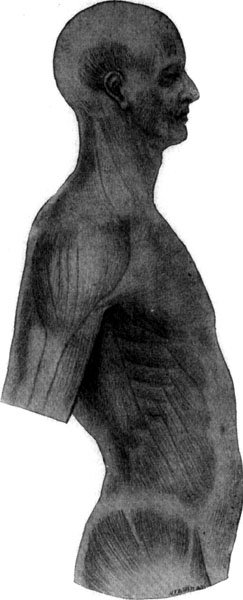

205 The Muscle-Sheet

(Greatly magnified)